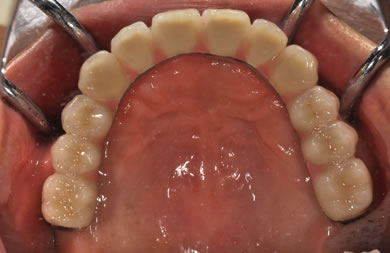

骨再生スピードインプラント治療+AGC連結セラミック治療

| 治療方針 | 上顎の歯周組織がかなり侵襲されているため、ソケットリフト法にて骨を回復させ、機能的回復だけでなく審美的回復も行うためにAGCハイブリッド連結ブリッジにて補綴処置を行う。 | ||||||||||||||||||||||||||||||||

| 治療内容 | インプラント12本(ソケットリフト+抜歯即日スピードインプラント)、ハイブリッドセラミック8本、AGCハイブリッドセラミック連結ブリッジ1装置、テンポラリーインプラント2本、遊離歯肉移植術 | ||||||||||||||||||||||||||||||||